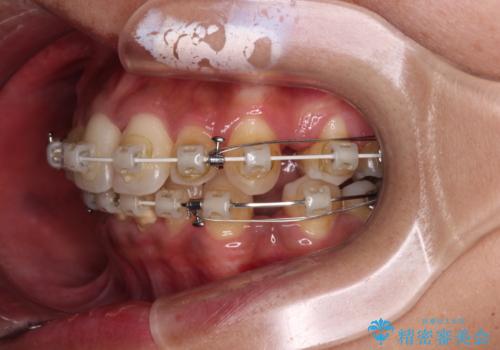

- 八重歯と上下前歯のでこぼこを気にして来院された患者様です。

上下前歯部叢生のスペース獲得のため、上下顎左右小臼歯各1歯(計4本)を抜歯して、ワイヤー装置にて矯正治療を行うこととしました。

上下の正中位置が大きくずれていたため、上下正中が合わないまま終了することが予想されましたが、思っていた以上にスムーズに歯が移動し、満足いただける仕上がりとなりました。